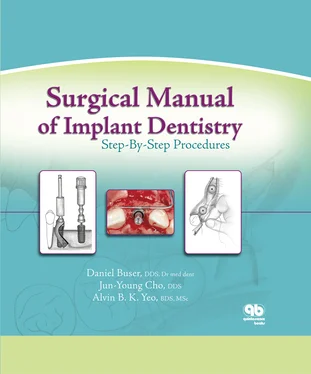

Fig 1-1Smoothing the alveolar crest following flap elevation.

Fig 1-1a Once the implant surgical site has been exposed, a large round bur is used to smooth and level the crest of the alveolar ridge.

Fig 1-1b All sharp edges and irregularities are removed by running the round bur across the alveolar ridge.

Fig 1-1c In this cross section, the irregular, narrow crest is smoothed to produce a flat, wide ridge, which is favorable for implant site preparation.